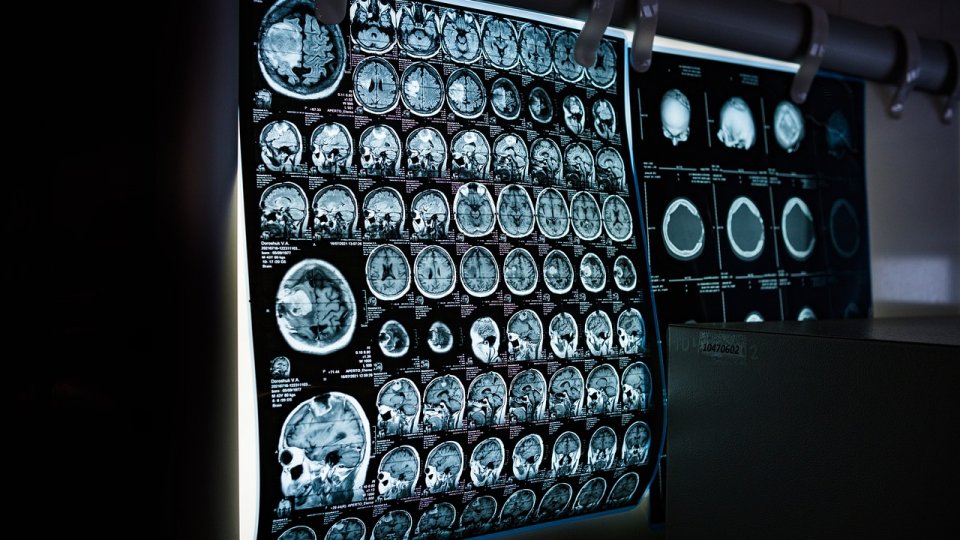

Există zeci de forme diferite de epilepsie, care nu se manifestă toate în același mod, dar care au toate anumite caracteristici comune", explică profesorul Fabrice Bartolomei*, șef al Departamentului de neurofiziologie clinică și epileptologie de la Spitalul Timone și vicepreședinte al Ligii franceze împotriva epilepsiei (LFCE). "Epilepsia este caracterizată de un simptom predominant și recurent: crizele epileptice. Acestea sunt manifestarea unor tulburări tranzitorii ale ritmurilor electrice ale creierului. Acesta este motivul pentru care diagnosticul epilepsiei se bazează pe analiza ritmurilor electrice ale creierului cu ajutorul EEG (Electroencefalograma)".

O electroencefalogramă poate confirma adesea diagnosticul de epilepsie.